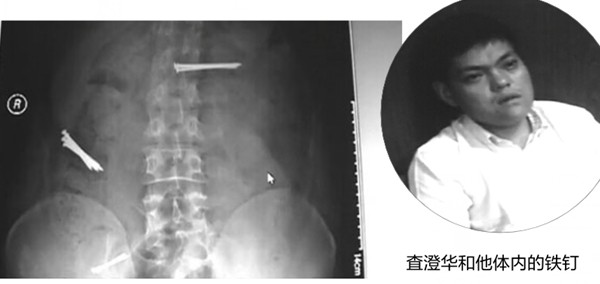

“吞钉男”现身蚌埠 多次吞钉四处编谎求助(图)

原标题:“吞钉男”现身蚌埠 多次吞钉四处编谎求助(图)

近年来,一位名叫